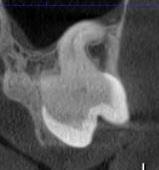

Часто причиною зубного болю є гайморит, і навпаки — причиною запалення пазух є хворий зуб. На звичайному знімку пазуха виглядає як темна пляма. На КТ ми бачимо стан слизової, наявність кіст або сторонніх тіл (наприклад, залишків пломбувального матеріалу), що критично важливо для правильного діагнозу.